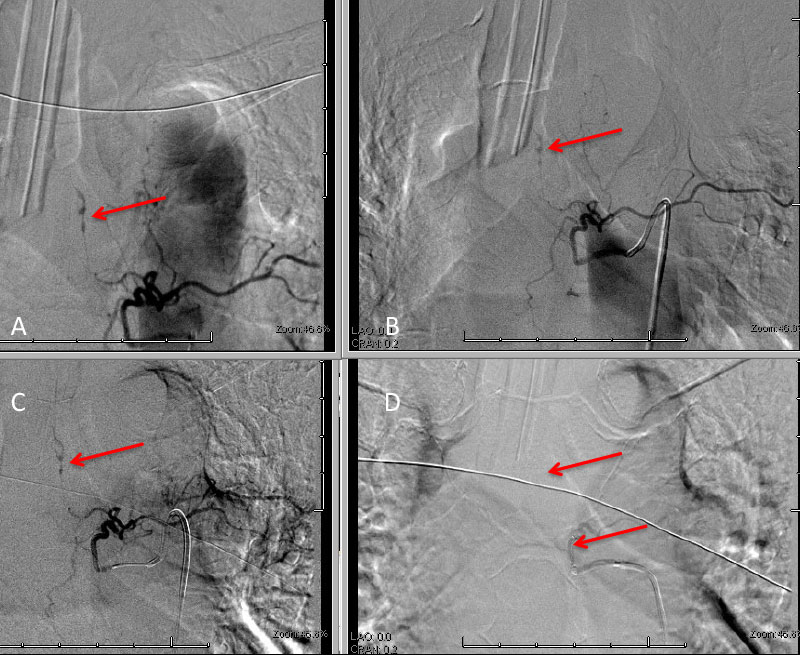

A man in his 60’s presented with acute onset of abdominal pain radiating to the back. The initial evaluation focused on GI abnormalities which were unremarkable. A screening CT scan of the brain was performed and suggested a possible subarachnoid hemorrhage which was subsequently confirmed on MRI and lumbar puncture (Figure 1A and 1B).

Figure 1: A) Non Contrast CT and B) MRI FLAIR studies demonstrate subtle Subarachnoid hemorrhage in the sylvian and parietal sulci (arrows)